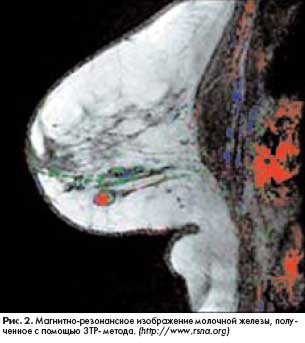

В основу другого нового метода, разработанного специалистами из Weizmann Institute of Science (Израиль), положена технология магнитно-резонансного сканирования с последующим цветовым кодированием полученных изображений. Исследование молочной железы производится в три этапа на протяжении примерно семи минут: непосредственно перед и дважды после введения контрастного вещества. Изображения обрабатываются с помощью специальной компьютерной программы, в результате чего создаются цветные снимки исследуемой области (рис. 2).

Красный цвет свидетельствует о злокачественности процесса (рис. 3а), а синий и зеленый - о доброкачественном росте (рис. 3б). Цветовое кодирование зависит от скорости накопления и выведения контрастного вещества из тканей. Поскольку злокачественная опухоль содержит много мелких вновь образованных кровеносных сосудов, кровоток в этой зоне усилен, а следовательно, контрастное вещество быстрее проникает и покидает опухоль. Новый диагностический метод, получивший название 3TP (Three Time Point), позволяет выявлять новообразования диаметром более 5 мм практически в 100% случаев.